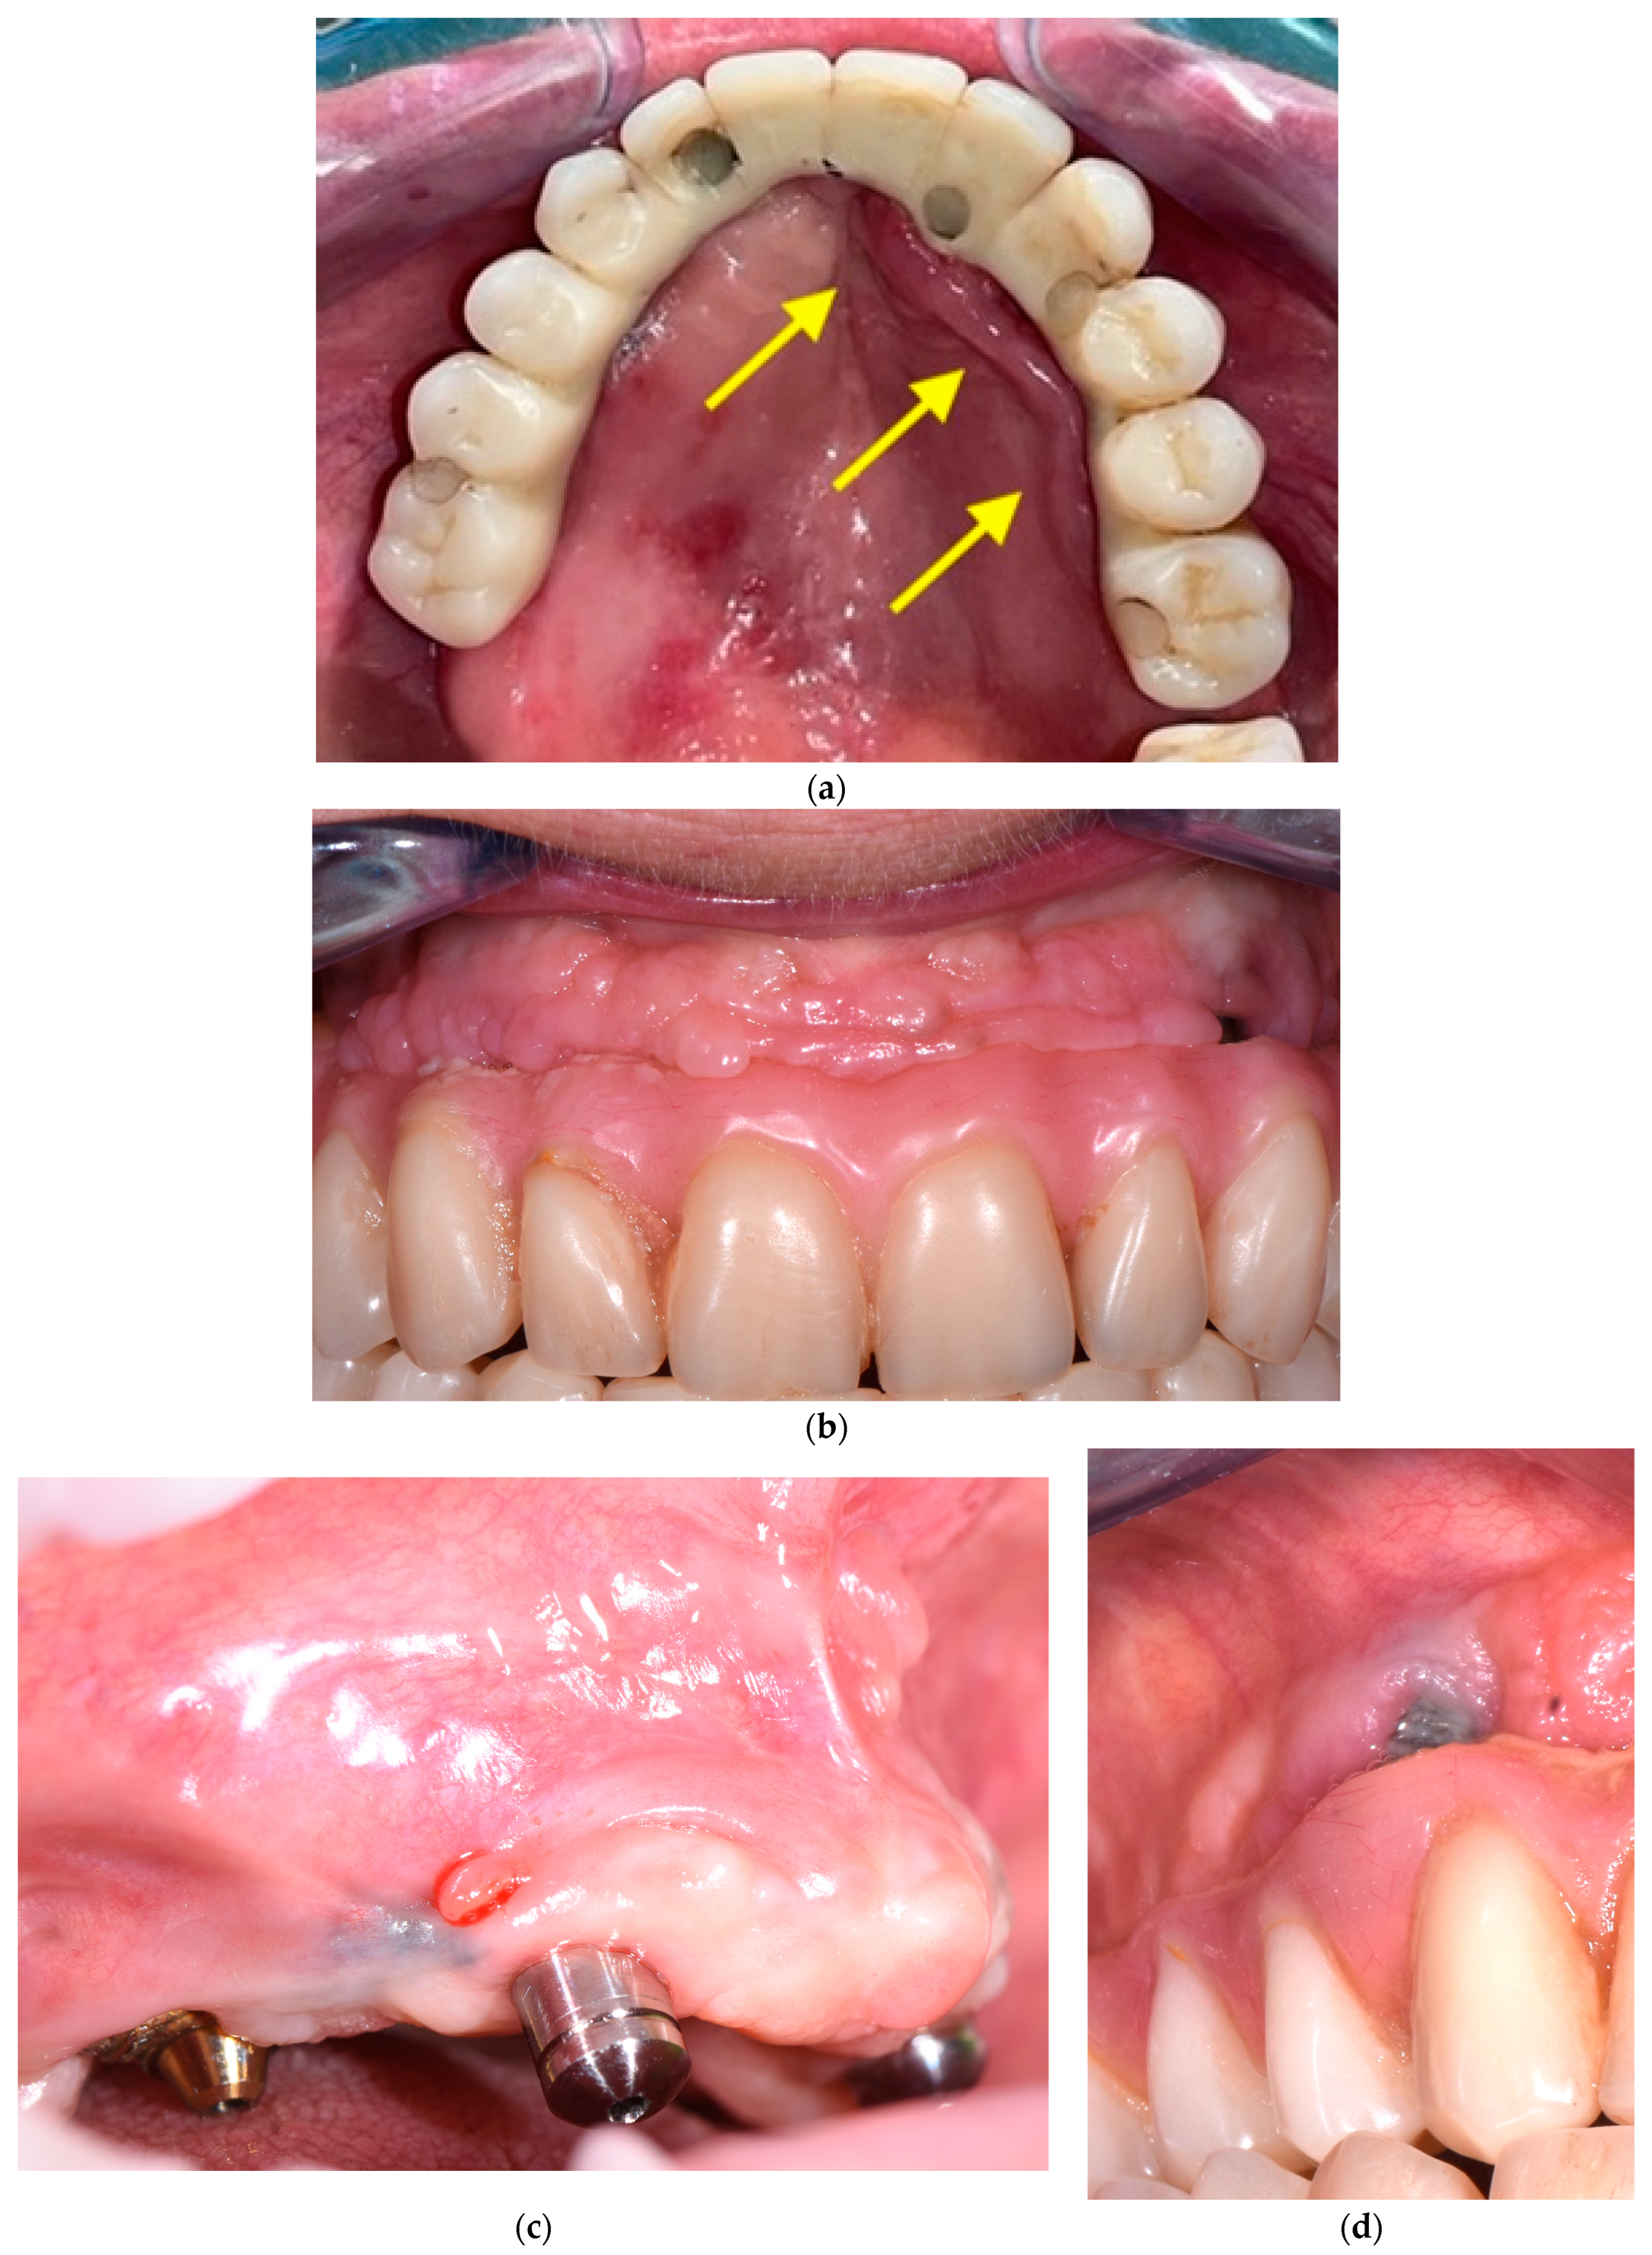

The second step consists of the examination of the soft tissues next to the implants and the prosthesis. In this phase, transmucosal decubitus (Figure 4a), fenestrations, hypertrophy (Figure 4b), fistulas (Figure 4c), and dehiscence (Figure 4d) must be identified and registered. In these cases, the prosthesis is unscrewed to assess peri-implant tissues and the morphology of the prosthodontic framework; investigations are conducted regarding any difficulties in maintaining hygiene due to inadequate space between the gums and the prosthesis. The devices to be used in this phase are retractors (i.e., Optragate, Ivoclar Vivadent, Schaan, Liechtenstein), gauze, and optical magnifiers.

Figure 4.

(a–d) Intraoral pictures of possible biological complications of zygomatic implants: decubitus (a), hypertrophy (b), fistulas (c), and dehiscence (d).